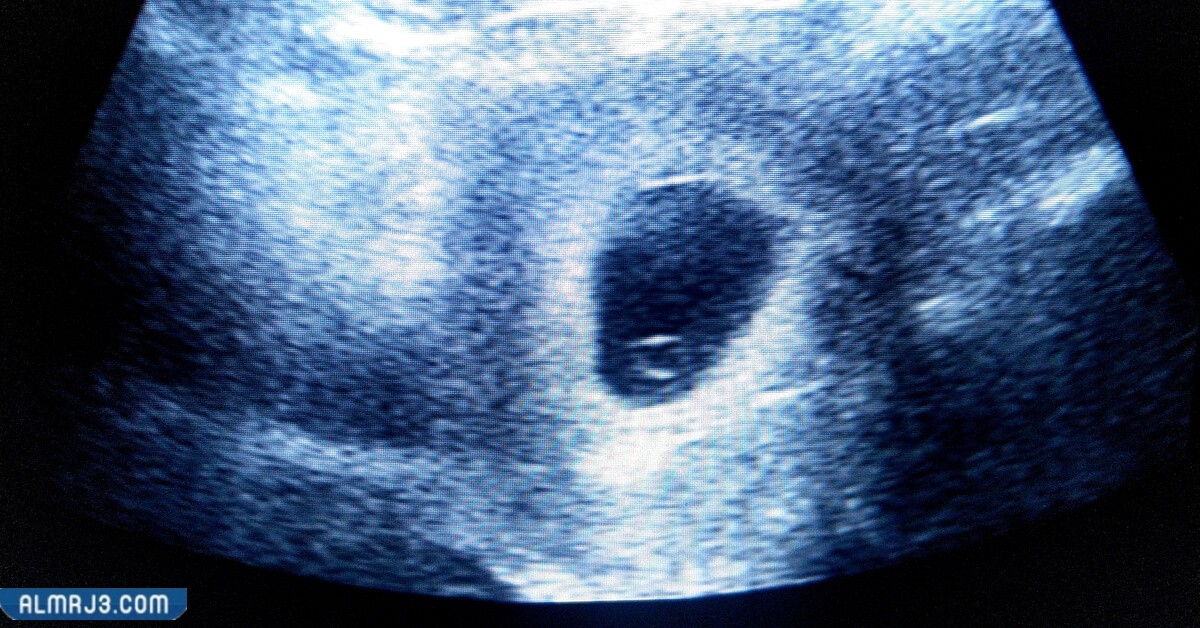

يعرف كيس الجنين، أو كيس الحمل (بالإنجليزية: Gestational sac)، على أنه الكيس المحيط بالجنين النامي في رحم الأم، وهو يحتوي على سائل يسمى بالسائل الأمينوسي (بالإنجليزية: Amniotic fluid)، ويظهر هذا الكيس، على صورة السونار (بالإنجليزية: Ultrasound)، على شكل إطار أبيض، محيط بمركز واضح، ويعد ظهور هذا الكيس على صورة السونار، أحد العلامات الأولى للحمل، إلا أنه لا يضمن كون الحمل صحي، أو أنه سيستمر بشكل طبيعي.[1]

يتكون كيس الجنين، بعد آخر دورة شهرية طبيعية للأم، بحوالي 5 إلى 7 أسابيع، ولذا فإنه عادة ما يظهر على صورة السونار المهبلي، عندما يكون عمر الحمل، قرابة 3 إلى 5 أسابيع، ففي ذلك الوقت، يكون معدل قطر كيس الجنين، يبلغ قرابة؛ 2 إلى 3 مليمتر، وعادة ما يكن رؤية هذا الكيس، بمجرد أن يصل مستوى هرمون الحمل (hCG)، ما بين؛ 1500 و 2000 ملي وحدة دولية/ مليلتر.[1][2]